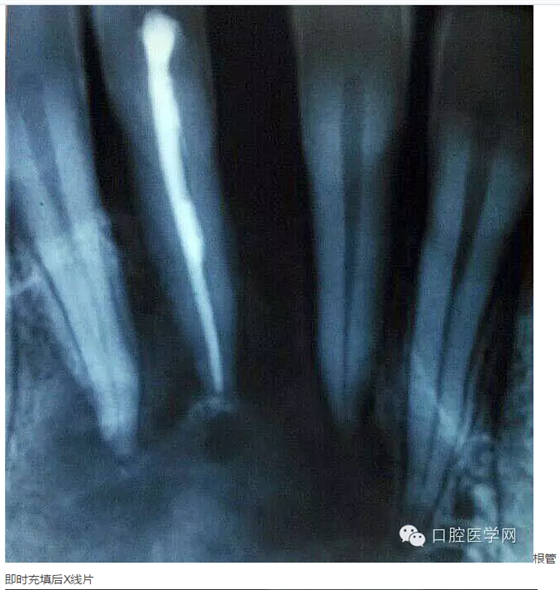

下面是一例 今年年初治療的下前牙根尖囊腫病例,患者因故未能按時復(fù)診,最近才來。